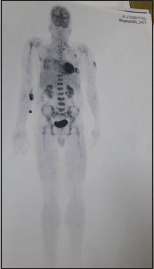

The recovery was phenomenal with creatinine lowering to 1.37 mg/dl and calcium to 9.6 mg/dl. The patient's appetite improved and the patient also received palliative radiotherapy of 30 Gys/10 fractions in a span 2 weeks during the stay. In view of radio imaging showing multiple lytic lesions and multiple air pockets, suspicion of plasmacytoma was made, and positron-emission tomography scan showed low-grade metabolic activity in multiple sites with multiple extensive lytic lesions confirming POEMS [Figure 7]. The patient was diagnosed to have POEMS fulfilling both mandatory criteria polyneuropathy and monoclonal plasma cell proliferative disorder. Two major criteria fulfilled were sclerotic bone lesion and elevated VEGF And four minor criteria fulfilled were splenomegaly, pleural effusion, endocrinopathy, and skin changes, although for the diagnosis of POEMS required only two mandatory criteria and more than one major criterion. The patient was discharged after 1 month of hospital stay with dramatic improvement with antibiotics, antifungal, antiviral, corticosteroids, and cyclophosphamide. The patient came for follow-up after 20 days and received the second cycle chemotherapy, with serum creatinine touching below baseline and skin changes almost disappearing. The patient has been advised for a timely follow-up in view of the good prognosis with the disease.

| Figure. 7 Positron-emission tomography scan showed low-grade metabolic activity in multiple sites with multiple extensive lytic lesions confirming polyneuropathy, organomegaly, endocrinopathy, M-spike, and skin changes